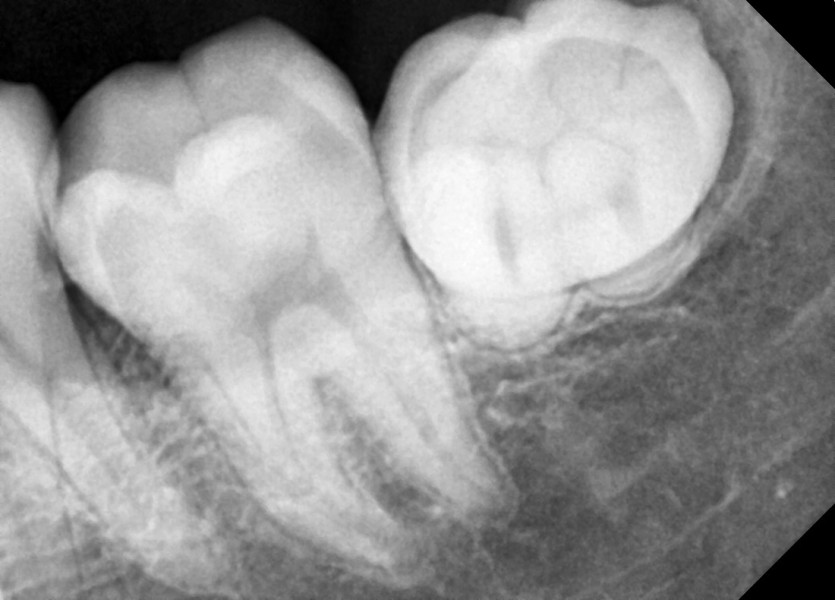

#38 사랑니 발치

구강 외과 전문의가 당일 발치했습니다.